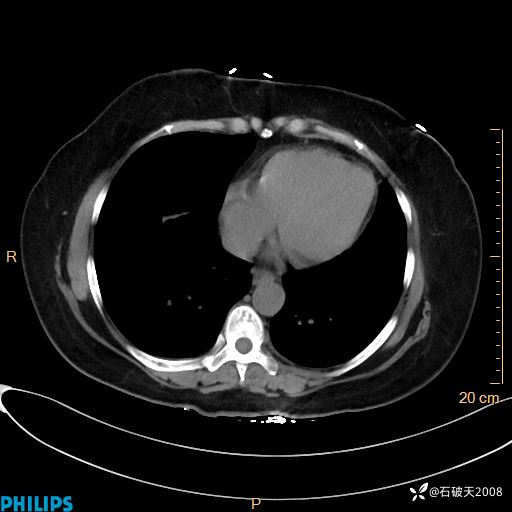

肺结节病?纵膈型肺癌?淋巴瘤?有点意思,欢迎围观

女 52岁 主 诉:咳嗽10余天,咳痰2天。

静脉期